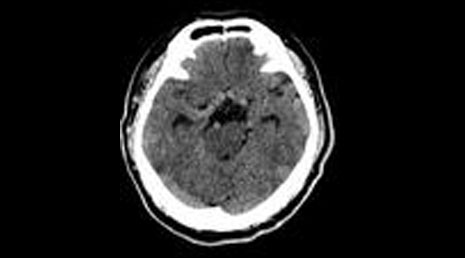

25. Cranial gunshot.